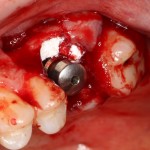

Все началось с воспаления, свищевого хода и удаления зуба:

Затем, мы готовим лунку и проверяем позиционирование импланта:

После чего аугментируем лунку. Для упаковки Bio-Oss Collagen очень удобно использовать аналоги имплантов:

Устанавливаем имплантат XiVE (Dentsply Implants):

Сразу на имплантат — временная коронка: